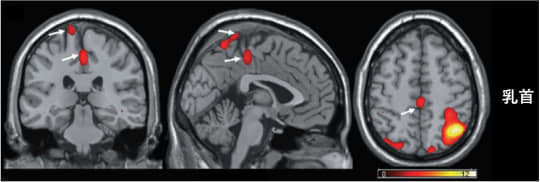

引用:TENGAヘルスケアより性器や乳首への刺激で、脳の中の体性感覚野がどのように活動するのかの実験結果があります。

2013年にアメリカのラトガース大学で「性器と乳首刺激時の脳活動」をMRIを使って測定した研究結果が存在します。

その結果によると、乳首への刺激によって、性器を刺激した時と同じ領域の脳活動が確認されています。つまり、乳首への刺激が、性器への刺激と同じ脳部位を活性化させるということが分かったのです。

セックスで乳房を愛撫する時に乳首は欠かせない場所であること。乳首は性器と同じポテンシャルを持っていること。ゆえに最後に刺激することで、より感度が上がる、ということがわかります。